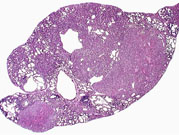

Multiple biliary and hepatocellular hyperplastic and neoplastic lesions in the liver of a 4-week-old transgenic mouse.

Confluent biliary and hepatocellular neoplasms totally occupying the left liver lobe of a 4-week-old transgenic mouse.